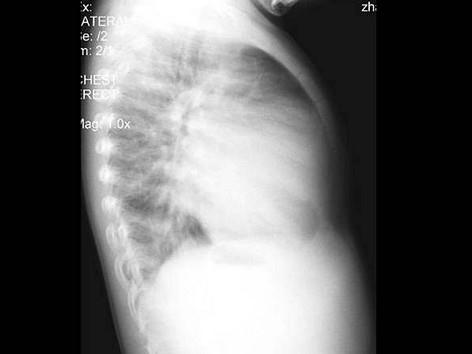

问题 男性,1岁零8个月,生长发育差,易患呼吸道感染,心悸气促,行心脏正、侧位片检查如图所示,错误的是 ( )

选项 A、房间隔缺损 B、室间隔缺损 C、肺纹理增多 D、侧位示心前间隙变窄,心后食管前三角间隙消失 E、正位示心影向两侧扩大,心尖左移

答案 A